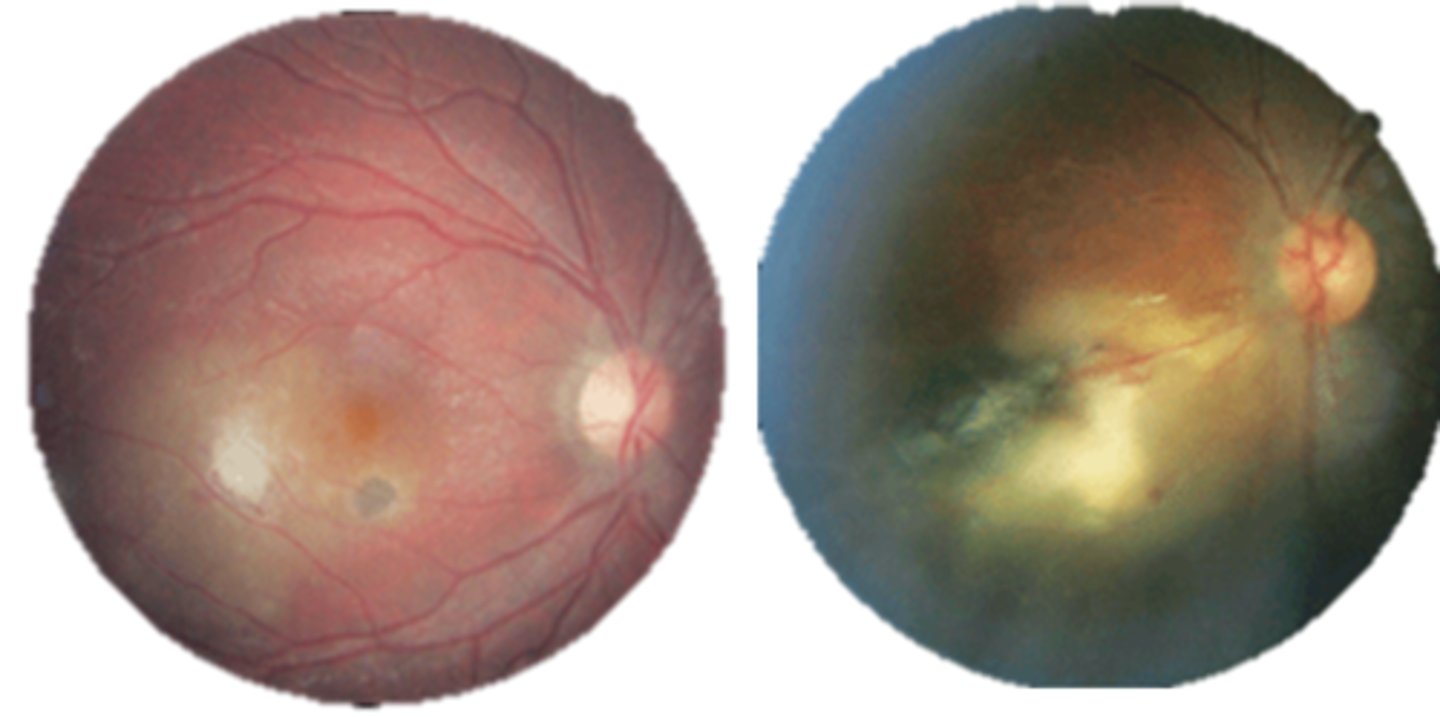

What finding of toxoplasmosis is seen in A/B?

retinitis turns into hazy scar with nerve pallor

What finding of toxoplasmosis is seen in C/D?

scarring overtime with VA loss/scotoma

What findings of toxoplasmosis are seen here?

retinal vasculitis

exudative scar

focal, hazy vitritis and retinitis

What findings of toxoplasmosis are seen here?

latent scars